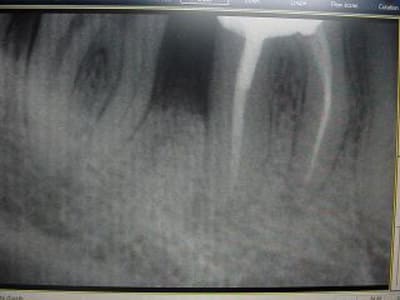

ci joint des retro de mars 2001 et aout 2003 de 46 qui montre l'evolution du cas..

D'autant que sur tes rétro la lésion évolue autour d'une dent, la 46, de façon évidente alors que 47 n'a pas bougé.

bon, je suis loin d'etre d'acc avec vous consernant l'endo: regardez l'evolution de la lesion, de 2001 à 2003, sur les retro: il me semble très peu probable que l'endo ( pas top, ok mais d'apparence pas si tocarde) soit en cause. On voit en 2001 une atteinte distale, clairement paro.